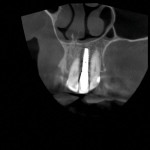

A 78-year-old female patient presented to the practice for an emergency visit because her left lateral incisor (tooth No. 10) had fractured at the gumline. She reported that she was "simply biting into a sandwich when her tooth broke off." The patient had a long history of consistent dental care throughout her life, and more than 30 years ago, tooth No. 10 had been previously restored with a root canal treatment, post and core buildup, and a porcelain-fused-to-metal (PFM) crown. Upon examination, it was noted that tooth No. 10 was fractured with no coronal tooth structure left and that a vertical root fracture was present. The tooth was deemed non-restorable. Treatment options were presented to the patient, and the risks and benefits of an implant-supported restoration versus a fixed partial bridge were discussed. If possible, the patient decided that she would like an implant placed. Her fractured PFM with its intact post and core was temporarily re-cemented that day and the patient was appointed to return for records.